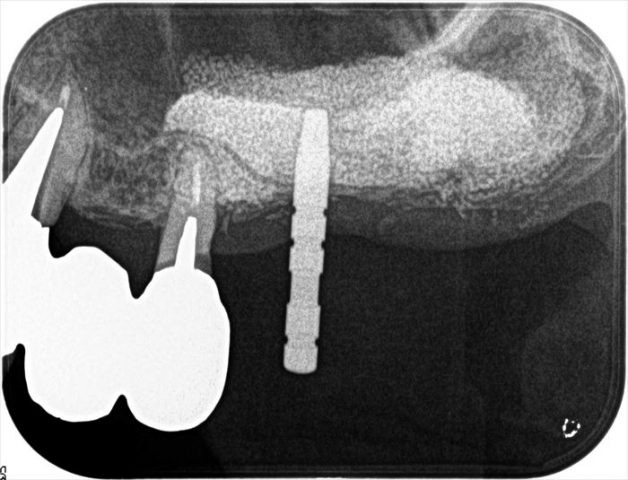

左上大臼歯部分に2本のインプラントを埋入します。

過去にサイナスリフト(上顎洞の骨増生)を行っています。

埋入時にはソケットリフトをさらに行い、骨の幅を最大限に使えるようにします。

まずは安全な深度までドリリングを行い、深度ゲージを挿入してレントゲンを撮影します。

レントゲンにて方向が予定通りであることを確認できましたので

オペ終了時のレントゲン写真です。

粘膜の厚さを把握することで埋入深度をコントロールします。